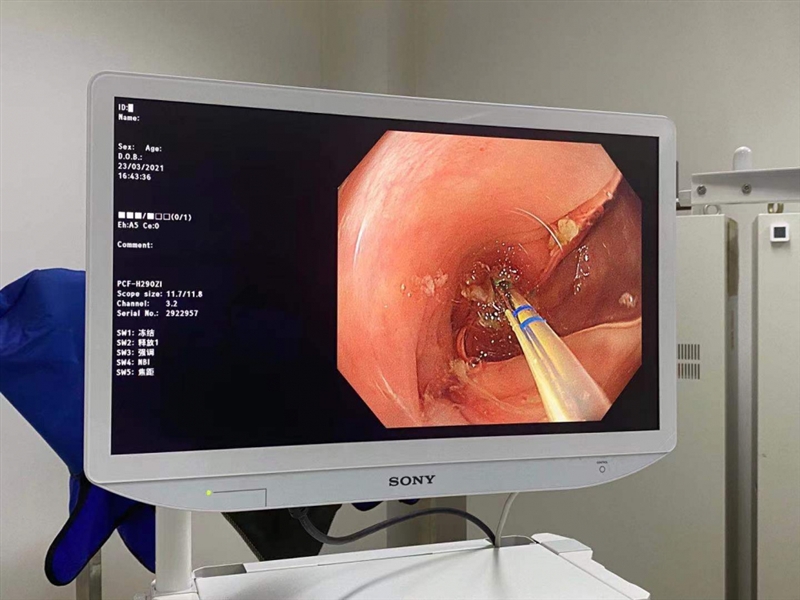

1.内镜下阑尾腔插管:正常的阑尾开口部都被Gerlach’s瓣覆盖,通过内镜前端的透明帽的帮助下,推开Gerlach’s瓣(黄箭头),并进行阑尾腔插管。当黄斑马导丝及导管置入阑尾腔时,可见脓性分泌物涌出。随之进行阑尾腔冲洗。